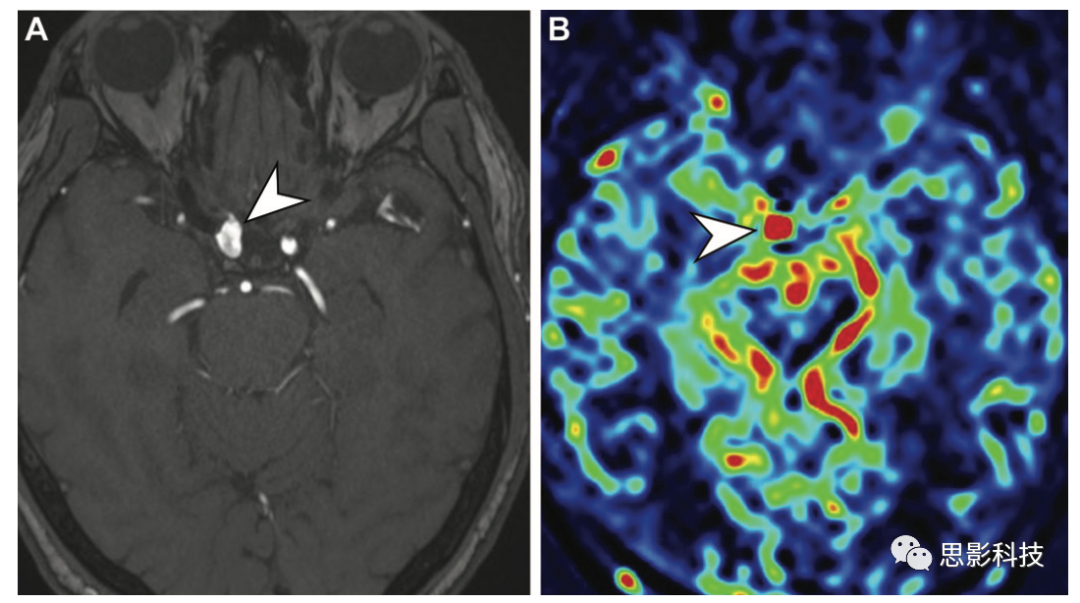

血管母細(xì)胞瘤 血管母細(xì)胞瘤是一種高度血管化的低級(jí)別腫瘤,通常表現(xiàn)為囊性病變,伴有顯著增強(qiáng)的壁結(jié)節(jié)或?qū)嵭圆∽儯T诤箫B窩內(nèi)含有血流空隙(60%的患者)。它可以作為孤立性病變或多發(fā)性病變發(fā)生,也可以與其他內(nèi)臟腫瘤合并,作為von Hippel-Lindau綜合征的一部分(14)。血管母細(xì)胞瘤的絕對(duì)和相對(duì)TBF較高,TBF總血流量明顯高于膠質(zhì)瘤、腦膜瘤和神經(jīng)鞘瘤。

14 48歲男性von Hippel-Lindau綜合征患者的小腦和視網(wǎng)膜血管母細(xì)胞瘤。

(A)軸位高分辨率增強(qiáng)后T1加權(quán)成像顯示右側(cè)小腦邊界清晰的均質(zhì)囊變(低信號(hào)區(qū)域),壁結(jié)節(jié)明顯強(qiáng)化,代表一個(gè)小腦血管母細(xì)胞瘤(白色箭頭),另外兩個(gè)小血管母細(xì)胞瘤(箭頭),以及一個(gè)左眼有強(qiáng)化病變的視網(wǎng)膜血管瘤(黑色箭頭)。

(B)ASL MRI顯示所有四個(gè)血管母細(xì)胞瘤的實(shí)體成分(白色和黑色箭頭)的灌注增加,可與單純囊性病變(低信號(hào)區(qū)域)相區(qū)別。